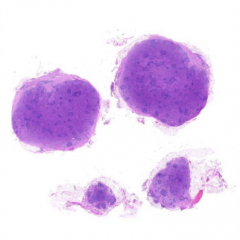

| 大体所见: | 颈部淋巴结4枚,直径0.2cm,0.4cm,0.8cm和1cm。 |